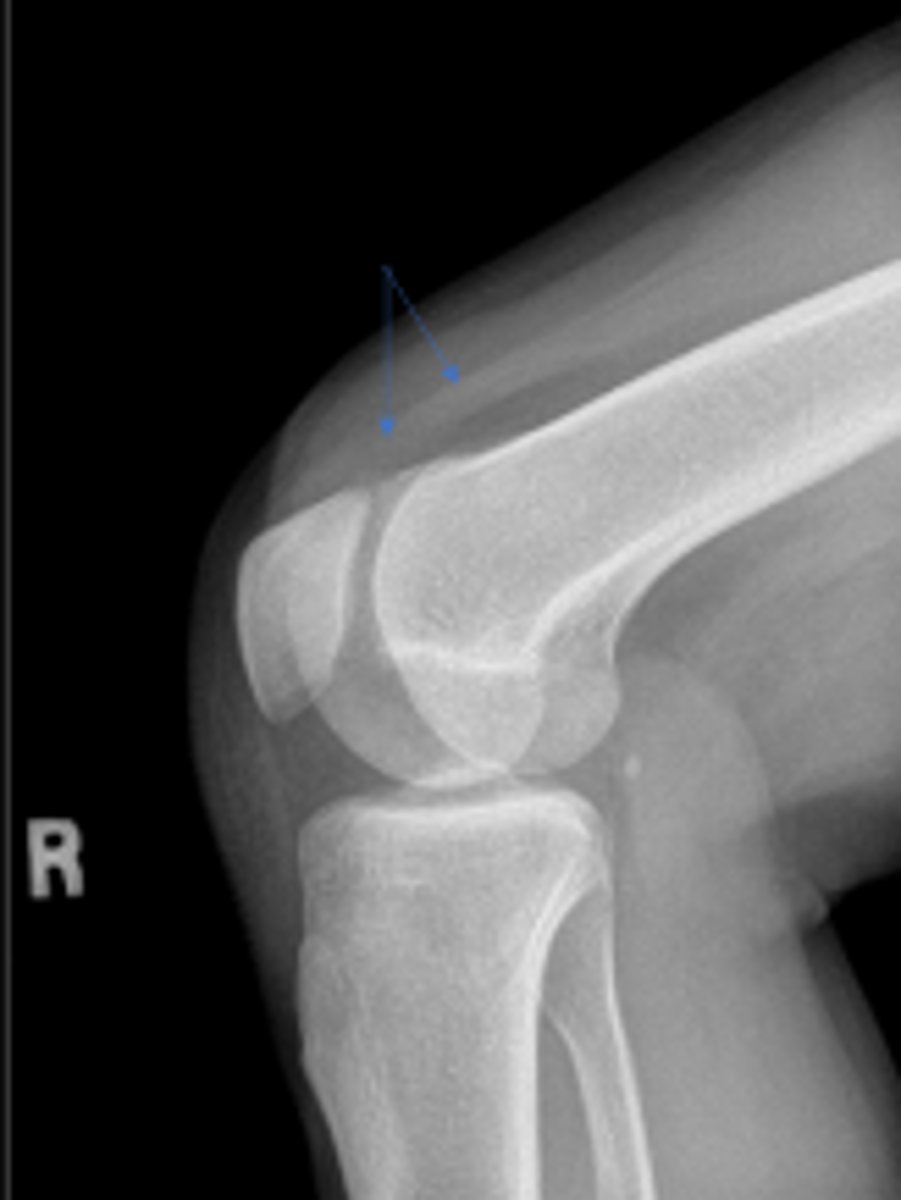

What is the name of the radiographic view?

Right patellofemoral joint space

What joint space is the arrowing pointing to?

Right patellar ligament

What is outlined?

Right quadriceps tendon

Right patella

Tuberosity of the right tibia

What area of the tibia is pointed to by the arrows?